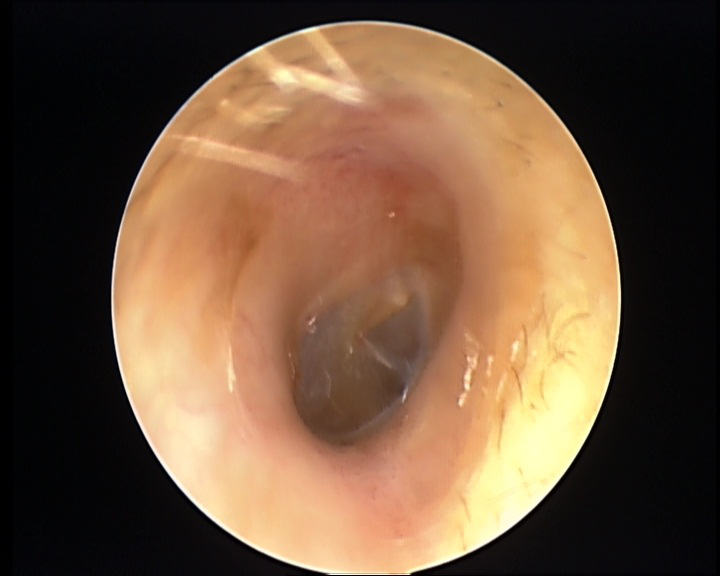

医生检查发现,他的双侧耳道表面布满密密麻麻的白色绒毛物体,被诊断为“外耳道真菌病”。

△治疗前原来,前几天小思去当地采耳店享受了一次采耳服务。